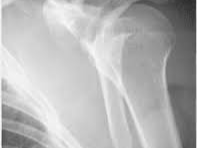

어깨뼈 골절은 어깨 주변을 구성하는 여러 뼈 중 하나가 부러지는 상태를 의미합니다. 어깨는 단순한 관절이 아니라 여러 뼈와 인대, 근육이 복합적으로 연결된 구조이기 때문에 골절의 종류도 다양하게 나타납니다. 흔히 발생하는 골절 위치는 견갑골, 쇄골, 상완골 근위부입니다. 특히 낙상 사고나 교통사고에서는 상완골 근위부 골절이 자주 발생합니다.

- 초기 진단

- X-ray 촬영

- CT 검사

- 골절 위치 확인